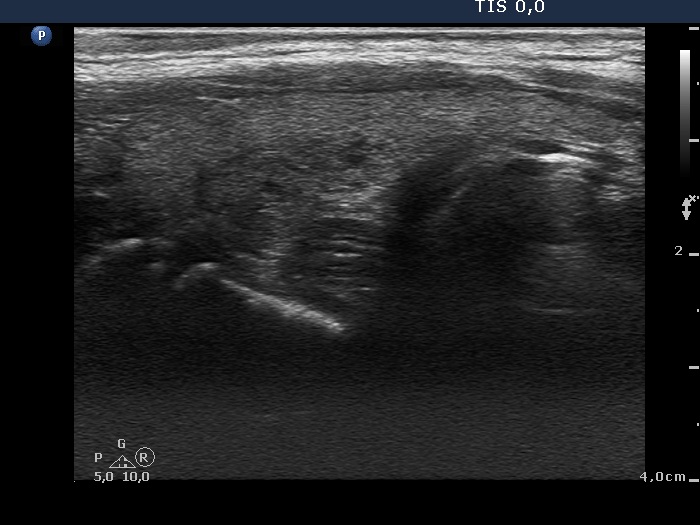

Follow-up examination 3 months later (2nd row of images):

Clinical presentation: The complaints of the patient ceased.

Palpation: The thyroid was not tender, both lobes were firm.

Functional state: hypothyroidism with TSH 2.98 mIU/L and FT4 7.56 pM/L. CRP 1.9 mg/L.

Ultrasonography: The proportion of hypoechogenic areas has decreased. The vascularization became normal.